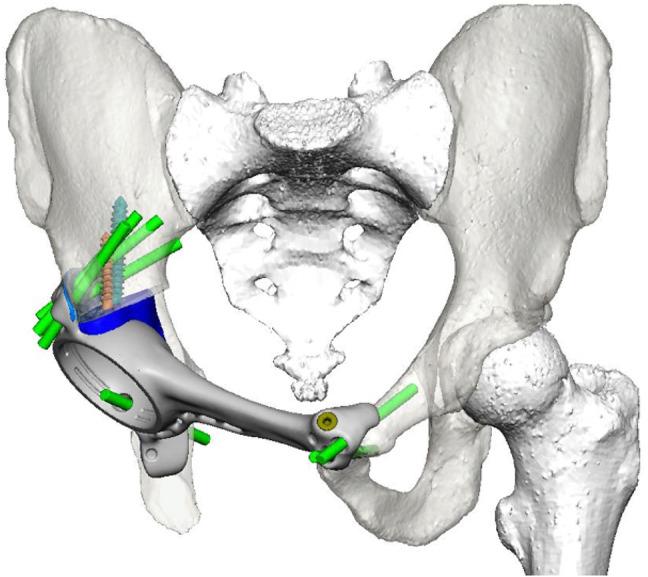

Access to custom 3D printed pelvic implants (3DPI) is improving for application in both arthroplasty revision and tumour reconstruction. There is limited evidence regarding the safety and outcomes of such implants for large bony defects of the pelvis. The aim of this study is to report the incidence of complications, patient mortality and implant survival following pelvic reconstruction using custom 3Dprinted prostheses in the setting of extensive pelvic bone defects following pelvic tumour resection or failure of total hip arthroplasty (THA).

One hundred and six procedures were completed (Revision THA = 33; Tumour Pelvis = 73) with a median follow up of 4.1 years, ranging from 0.6 to 10 years. Acetabular loosening was the most frequent indication for the Revision THA cohort, while indications for tumour varied across primary presentations, metastases and failures of previous resection/reconstruction. Intraoperative complications were observed in 4.1% (95%CI 1.1-12.3) of Tumour Pelvis cases. Overall implant retention was 96% (90-99). No mortality events were observed in the Revision THA cohort, with 5-year patient survival 79% (70-90) in the Tumour Pelvis cohort. Procedure-survival free from periprosthetic infection was 86% (74-100) in the Revision THA cohort and 85% (76-95) in the Tumour Pelvis cohort. Modelling adverse events using multistate survival models in both cohorts revealed complex time-varying presentation of adverse events, with a significant burden of reoperations and local tumour recurrence in the Tumour Pelvis cohort.

3DPIs are a safe and viable option for complex reconstruction of the pelvis across a range of oncological and non-oncological indications. The initial results of the present study provide important information to aid in counselling patients about such procedures and allocating healthcare resources for ongoing care. Further work is required to document functional and biomechanical outcomes in these patient populations.

定制3D打印骨盆植入物(3DPI)在关节置换翻修术和肿瘤重建中的应用越来越广泛。关于此类植入物用于骨盆大骨缺损的安全性和效果的证据有限。本研究的目的是报告在骨盆肿瘤切除或全髋关节置换术(THA)失败后出现广泛骨盆骨缺损的情况下,使用定制3D打印假体进行骨盆重建后并发症的发生率、患者死亡率和植入物存活率。

共完成了106例手术(翻修THA = 33例;肿瘤骨盆 = 73例),中位随访时间为4.1年,范围从0.6年至10年。髋臼松动是翻修THA队列中最常见的指征,而肿瘤患者的指征因原发表现、转移和既往切除/重建失败而有所不同。在4.1%(95%CI 1.1 - 12.3)的肿瘤骨盆病例中观察到术中并发症。总体植入物保留率为96%(90 - 99)。在翻修THA队列中未观察到死亡事件,肿瘤骨盆队列中5年患者生存率为79%(70 - 90)。翻修THA队列中无假体周围感染的手术生存率为86%(74 - 100),肿瘤骨盆队列中为85%(76 - 95)。在两个队列中使用多状态生存模型对不良事件进行建模,结果显示不良事件呈现复杂的随时间变化情况,肿瘤骨盆队列中再次手术和局部肿瘤复发的负担较重。

3DPI是一种安全可行的选择,可用于一系列肿瘤和非肿瘤指征的骨盆复杂重建。本研究的初步结果提供了重要信息,有助于为患者提供此类手术的咨询,并为持续护理分配医疗资源。需要进一步开展工作以记录这些患者群体的功能和生物力学结果。